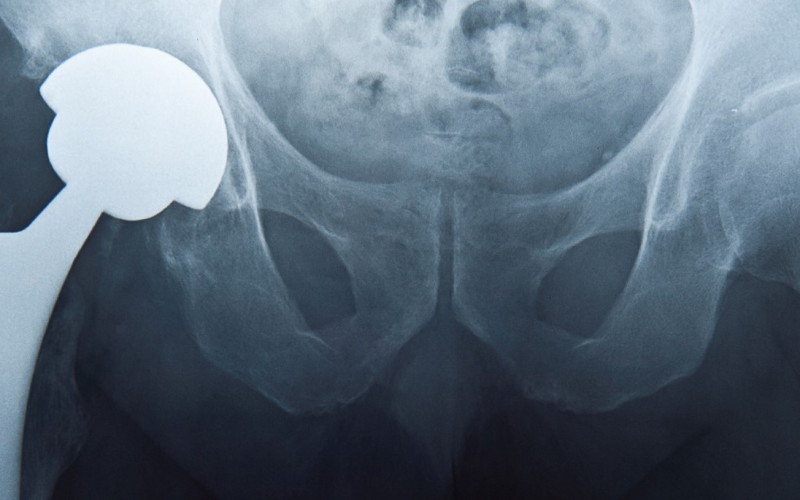

Brytyjska firma wycofała z rynku tysiące endoprotez stawu biodrowego. Wszczepiano je także w Polsce, ale o tym nasi pacjenci nic nie wiedzą

Część z tysięcy osób, którym od lipca 2003 r. do sierpnia 2010 r. wymieniono u nas operacyjnie zniszczony staw biodrowy, otrzymała endoprotezę firmy DePuy – jednej z dwóch serii uznanych potem za wadliwe, być może szkodliwe dla zdrowia.

Dwie wadliwe serie

DePuy International Ltd, brytyjska spółka należąca do holdingu Johnson & Johnson, jest znanym producentem endoprotez stawu biodrowego. W latach 60. jako jedna z pierwszych wprowadzała całościową wymianę tego stawu na sztuczny. Między rokiem 2003 a 2010 wyprodukowała i rozprowadziła w wielu krajach świata ok. 93 tys. protez stawu biodrowego ASR XL Acetabular System oraz ASR Hip Resurfacing System. Zakupiły je także polskie szpitale, a potem wszczepiły pacjentom. Ilu? Żadna instytucja medyczna, do której się zwróciłam, nie przekazała mi takich danych. Wyjaśniano, że poszczególne szpitale sprowadzają endoprotezy indywidualnie. Znam szpitale, gdzie w tym czasie wszczepiono pacjentom kilkadziesiąt tego typu endoprotez, poznałam ortopedę, który założył ich ponad sto, przypuszczam więc, że w Polsce ma je co najmniej tysiąc osób. Być może znacznie więcej. Nie jestem pewna, czy ludzie ci wiedzą, kto je wyprodukował i jakiej są serii, ale metryczka z tymi informacjami powinna się znajdować w ich dokumentacji medycznej.

W sierpniu 2010 r. firma DePuy wycofała endoprotezy dwóch wymienionych serii, oferowane na rynku medycznym od lipca 2003 r., i powiadomiła o tym ich odbiorców. Akcentowała, że decyzja o wycofaniu produktów była dobrowolna, ale podjęto ją, gdy okazało się, że endoprotezy te zagrażają zdrowiu osób, którym je wszczepiono – u ok. 12-14% pacjentów trzeba było wadliwą protezę usunąć. Niektóre dane mówią, że w ciągu sześciu lat wadliwość implantu dała o sobie znać u niemal połowy pacjentów. Producent został zmuszony do pokrywania kosztów badań i leczenia tysięcy osób, wypłaca też odszkodowania.